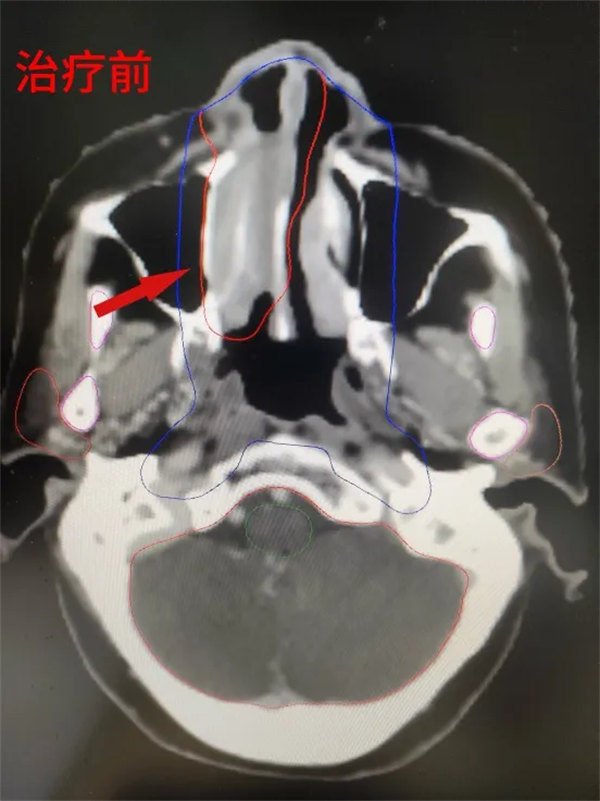

68歲的趙阿姨,2月前因“鼻塞及視物模糊”就診入院,經全面檢查后確診為右側鼻腔NK/T細胞淋巴瘤,明確診斷后血液腫瘤內科主任朱暉組織醫護團隊進行多次討論,并請放射治療科張世衡副主任醫師會診綜合評估,根據患者年齡、心肺功能、腫瘤分期、體能狀況,最終制定以放療序貫化療的治療方案,放射治療科醫護團隊立即為患者做好放療前準備:制模定位、勾畫靶區、制定計劃,并于第二天下午實施放療,在放療過程中,主管醫生侯蕊及張世衡醫生密切關注患者病情變化,為患者及家屬做好解釋,消除患者的消極情緒。經過25次的放療,患者鼻腔腫瘤明顯消退,趙阿姨高興地說:“自己鼻子不堵了,看東西也清楚了,對于后續的治療相當有信心”。